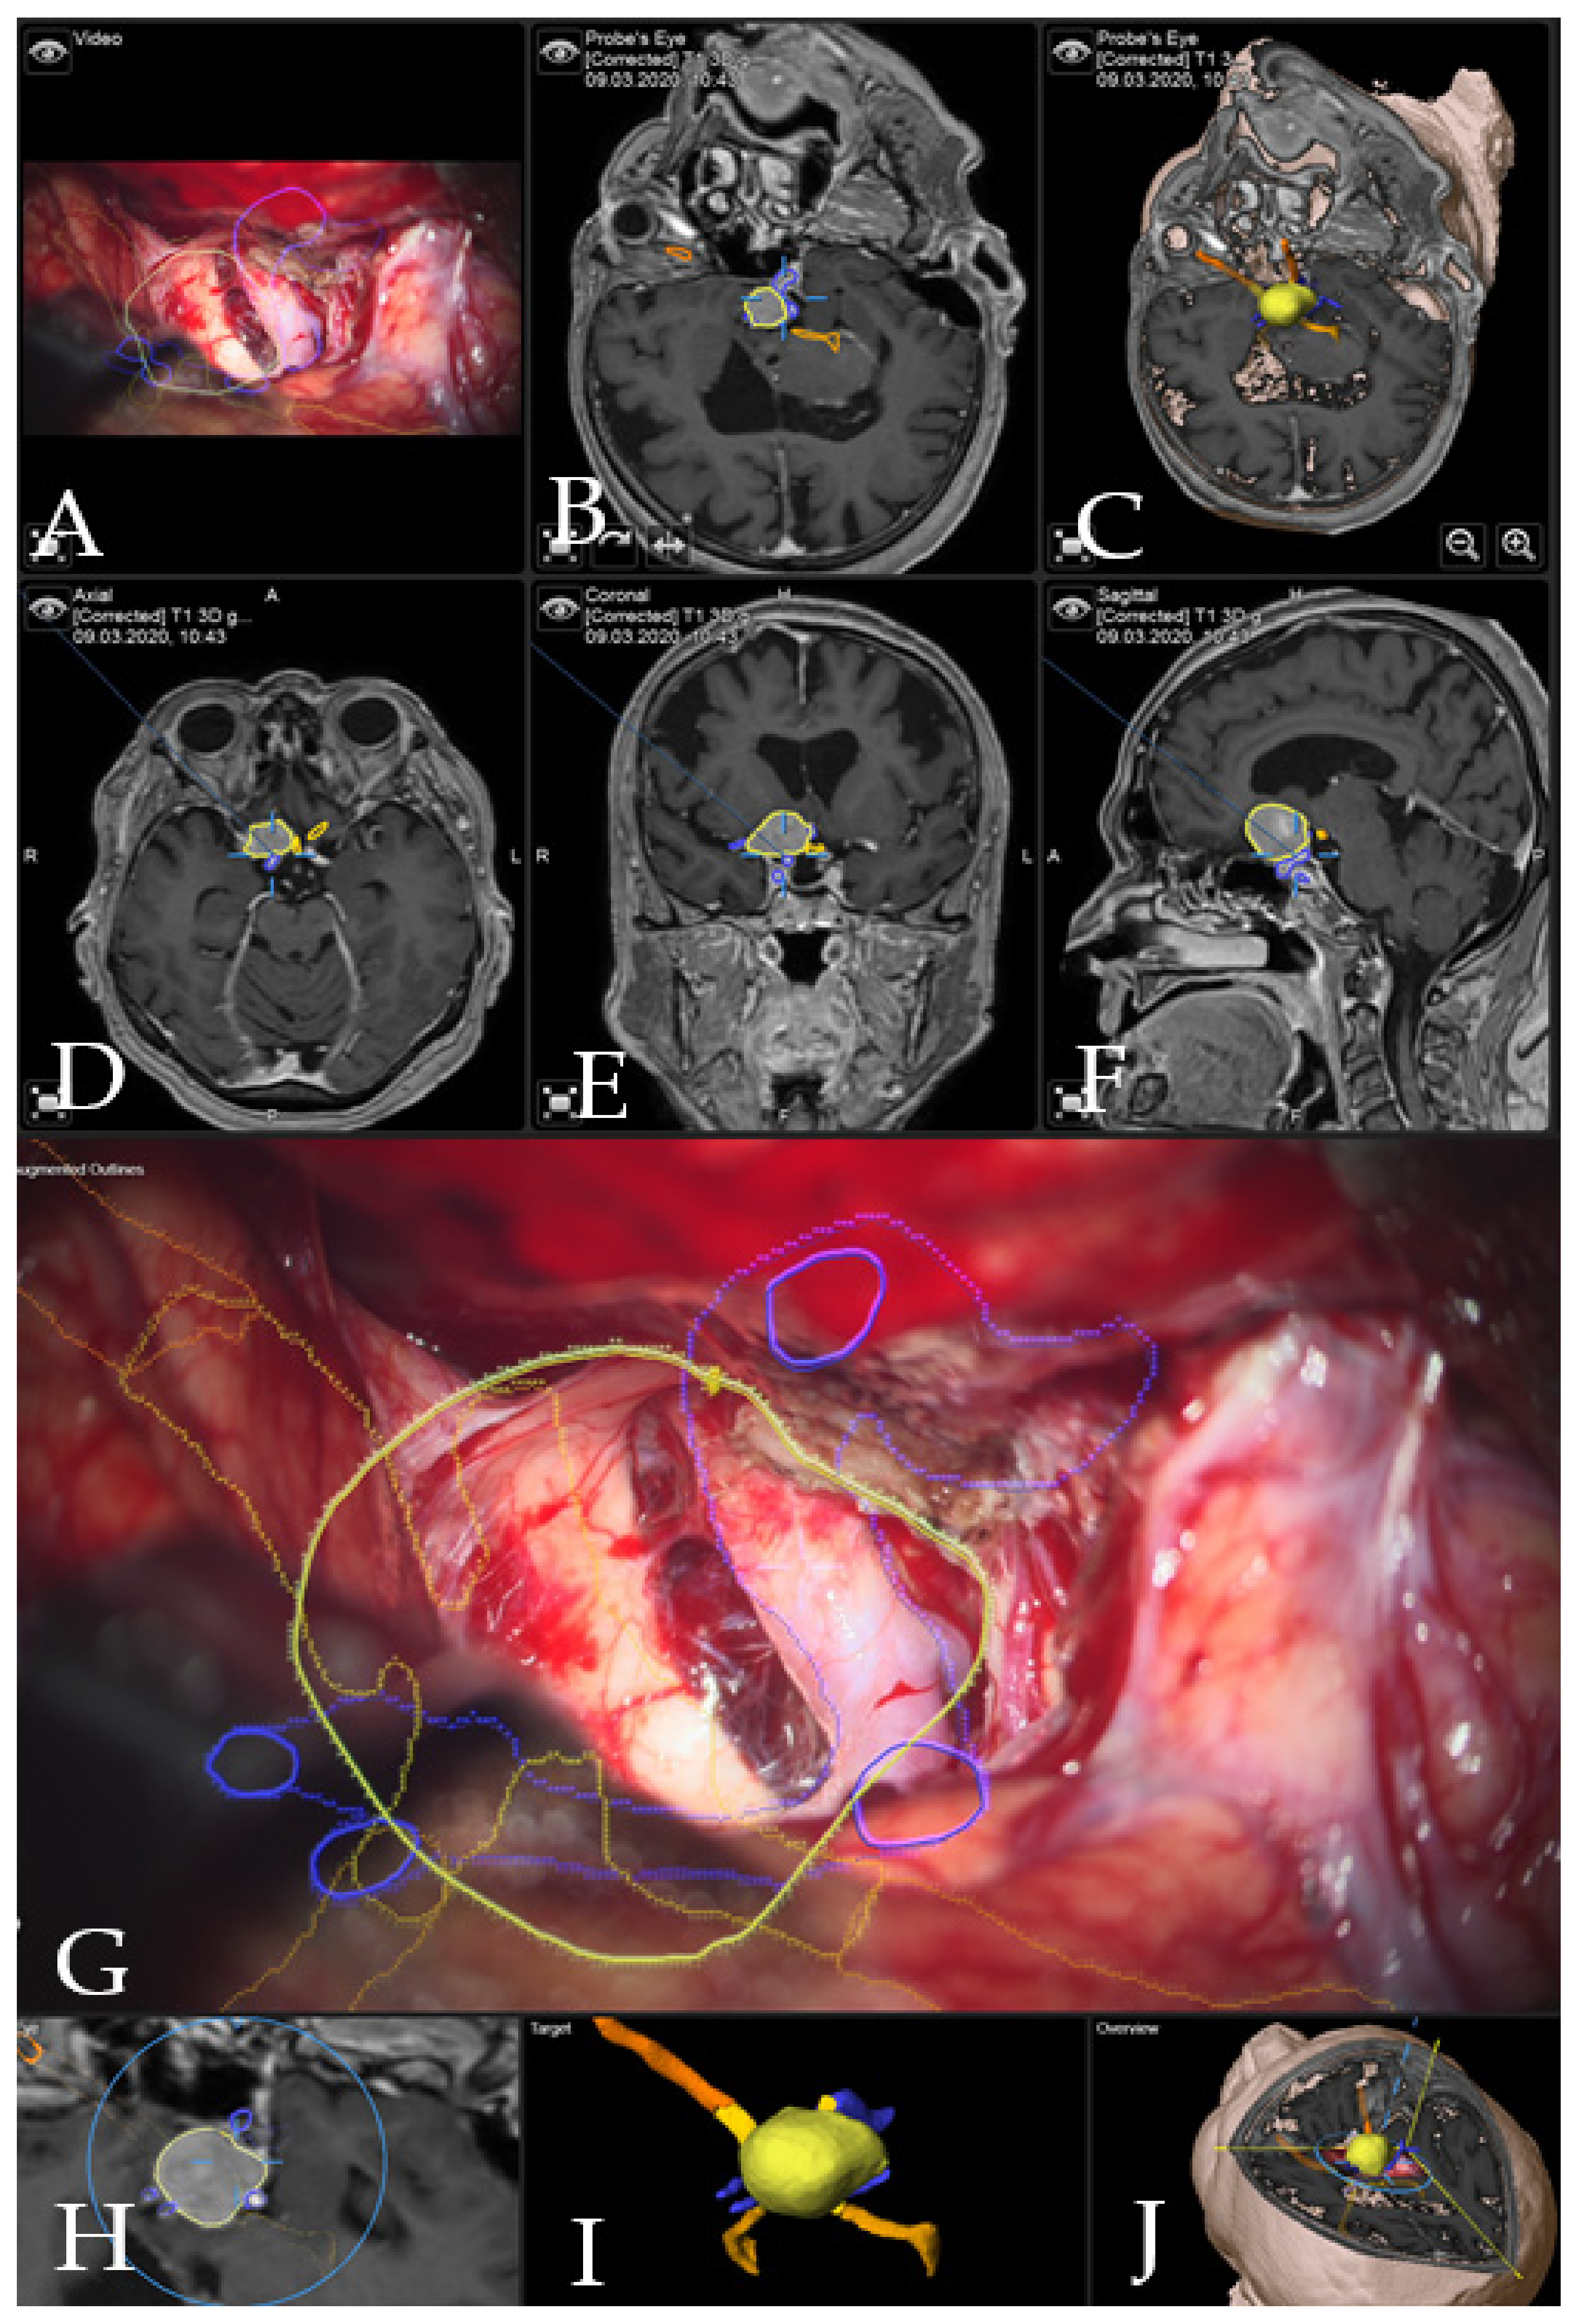

Illustrative Cases